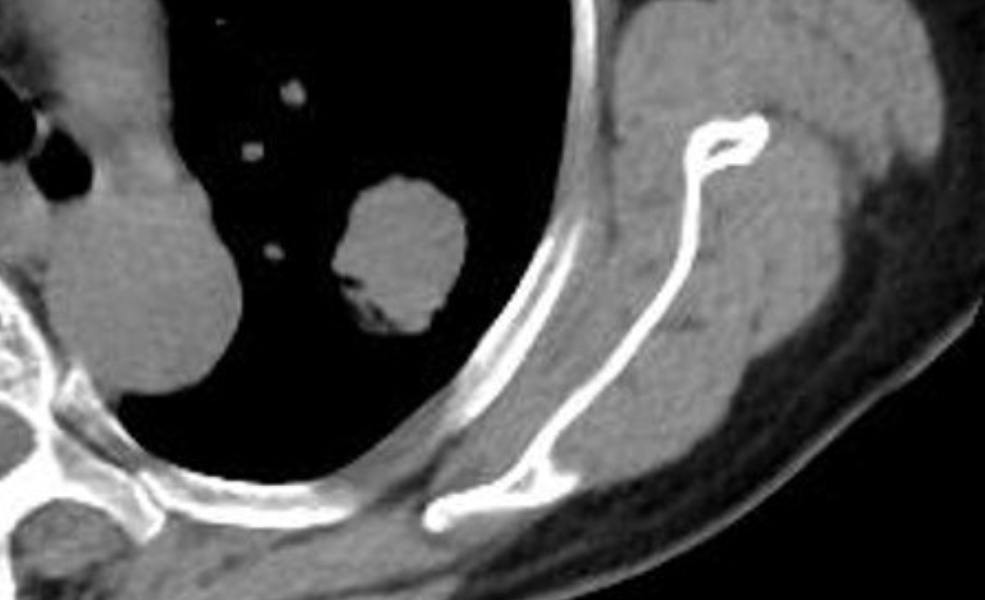

平扫CT肺窗

平扫CT纵隔窗密度约40HU

增强CT纵隔窗,肺结节密度增高至60HU,考虑恶性肿瘤

PET-CT显示病灶糖代谢摄取高,

诊断为恶性肿瘤